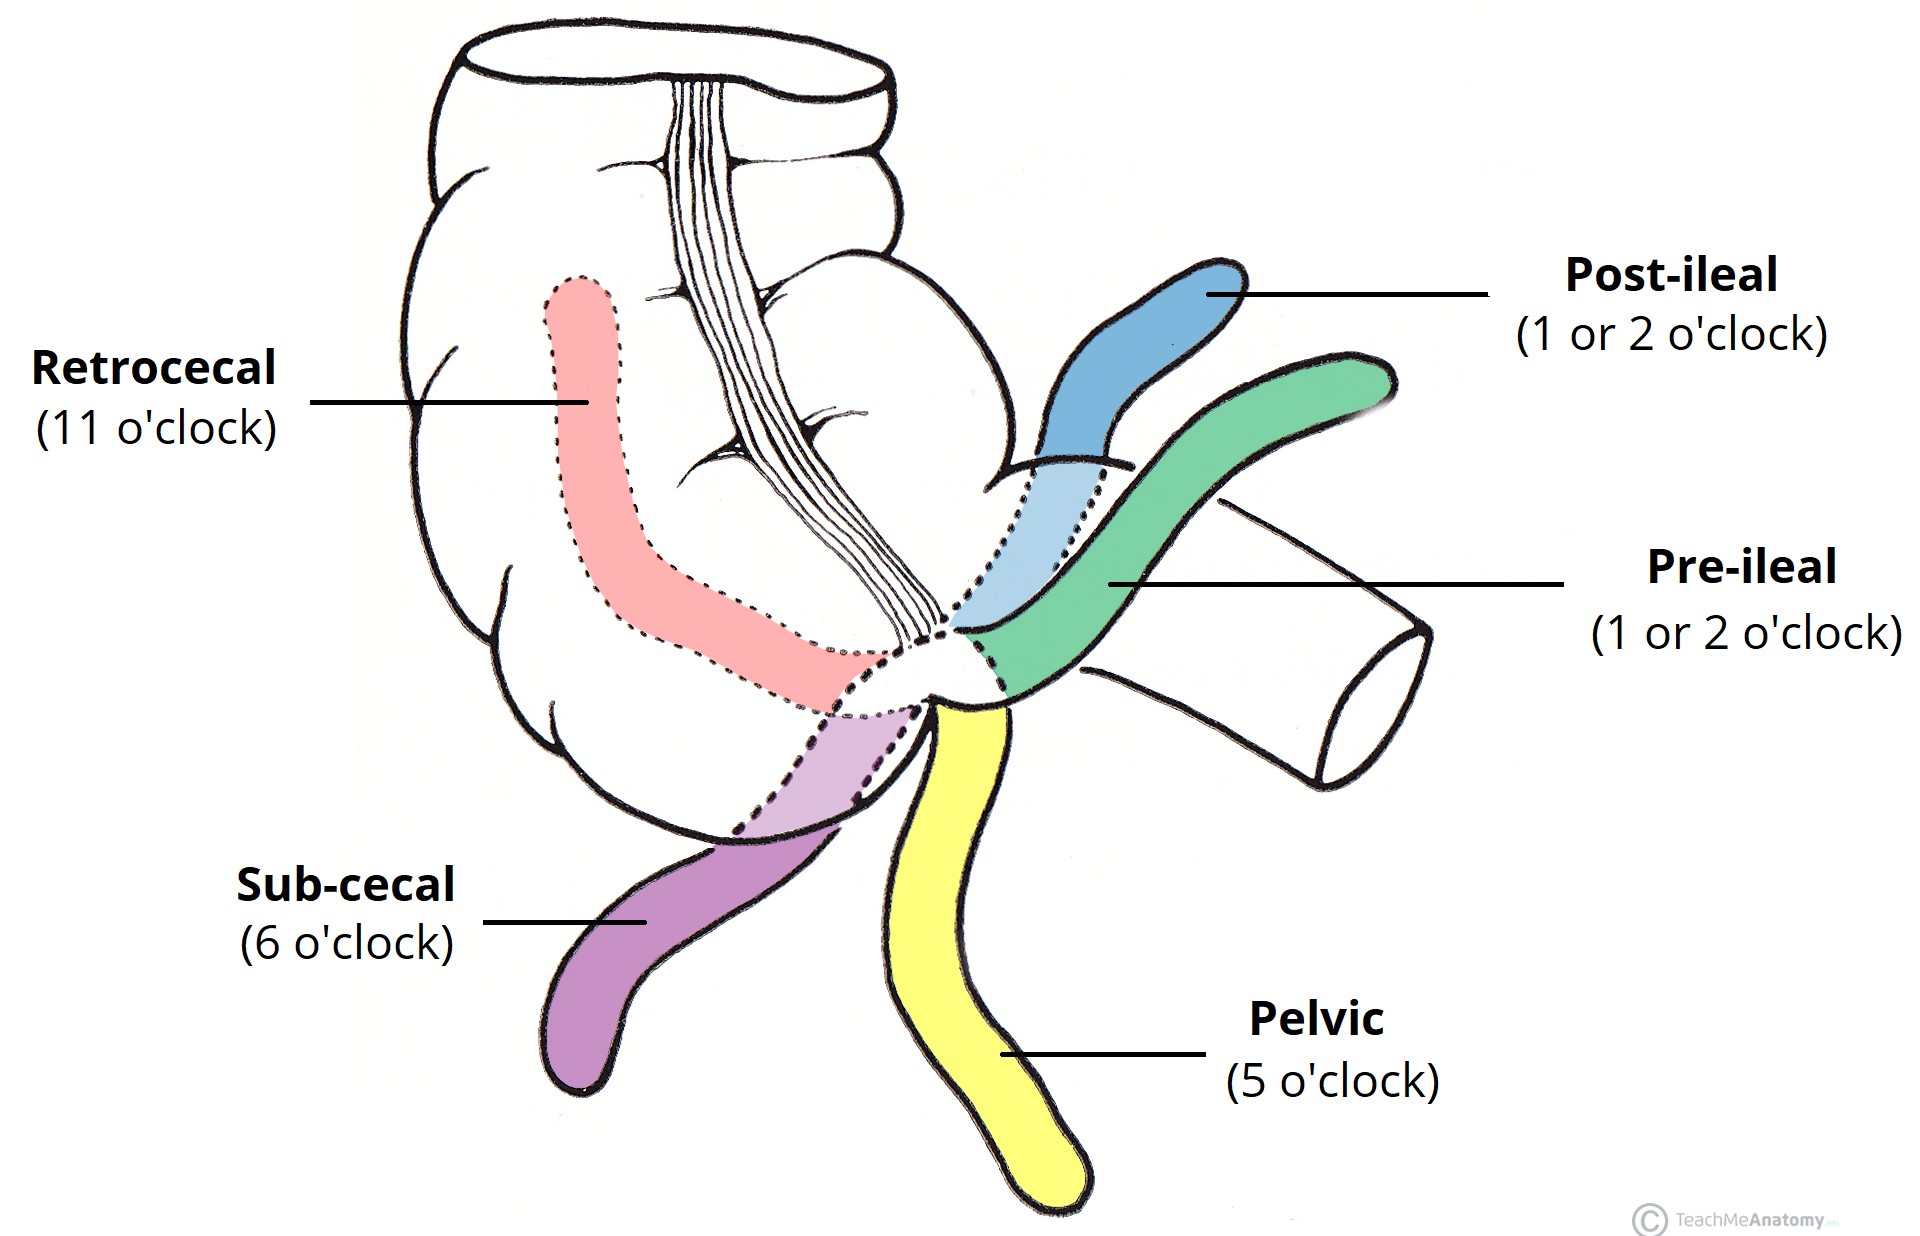

The Appendix Retrocecal Arterial supply Appendicitis TeachMeAnatomy

The appendix arises from the posteromedial surface of the cecum, approximately 2-3 cm inferior to the ileocecal valve, where the three longitudinal bands of the taeniae coli converge. It is a blind diverticulum which is highly variable in length, ranging between 2 and 20 cm. The appendiceal mesentery is called the mesoappendix 1,2.

The appendix is a narrow blind-ended tube that is attached to the posteromedial end of the cecum (large intestine). It contains a large amount of lymphoid tissue but is not thought to have any vital functions in the human body.. In this article, we shall look at the anatomy of the appendix - its anatomical structure and relations, neurovascular supply and lymphatic drainage.

Appendix Positions Retrocecal (*most common) GrepMed